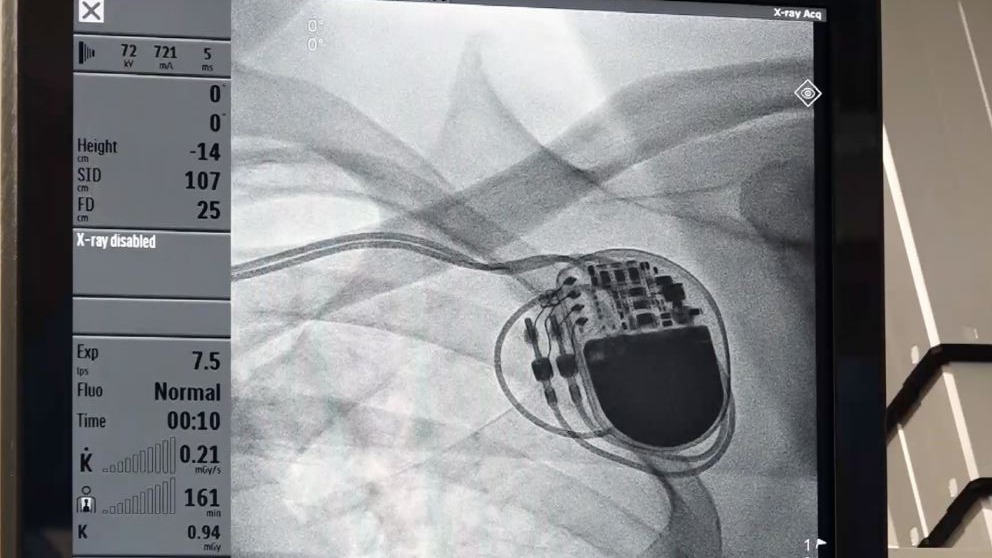

뇌경색을 앓은 김종백(63) 씨는 1년 반 동안 24시간 계속 시행되는 검사로, 뇌경색 원인이 심방세동이었음을 알아내 뇌경색 재발을 막을 수 있게 되었다. 단시간의 검사가 찾아내지 못하는 심장질환을 추적하는, 인체에 직접 넣는 삽입형 사건 기록기(ILR)의 의과학 세계를 알아본다.

심장박동기를 삽입하고 문제없이 생활하는 최영선(56) 씨와 심한 메니에르병으로 4차례에 걸친

수술을 받았지만 재활운동을 통해 일상을 되찾고 있는 배영명(69) 씨를 만나본다.